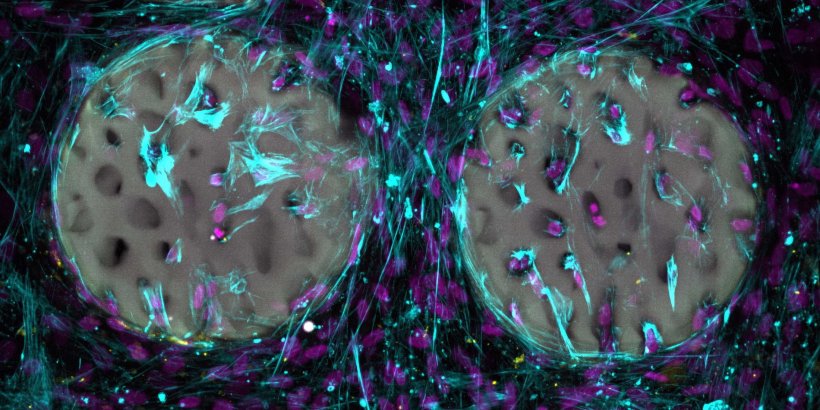

Bildquelle: Margherita Bernero / ETH Zürich

Per Laserlicht wird das Hydrogel sehr schnell zu einem Material mit mikroskopisch feinsten Strukturen verfestigt, damit knochenbildende Zellen es gut besiedeln können.

In ihrer Studie stellten die Forschende unter anderem komplex strukturierte Hydrogels her, die wie echter Knochen aussehen und ein feines Netz von Knochenbälkchen aufweisen. Als Vorlage dienten den Forschenden Bilder aus der medizinischen Bildgebung.

Bisher haben die Forschenden das Material erst im Reagenzglas getestet. Dabei zeigte sich, dass knochenbildende Zellen das strukturierte Hydrogel rasch besiedeln und beginnen, Kollagen zu bilden, ein wichtiger Bestandteil des Knochens. Die Tests zeigten weiter, dass das Material biokompatibel ist und die knochenbildenden Zellen nicht schädigt. Die Forschenden haben das Basismaterial patentieren lassen und möchten es der medizinischen Industrie zugänglich machen.